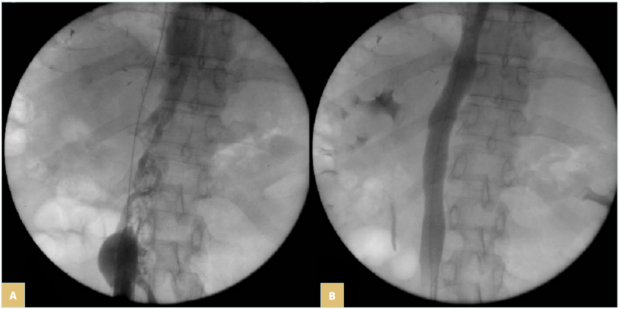

Once the lesion is crossed (Figure 4A and 4B), super stiff or extra stiff guidewire and then a larger sheath are inserted (10-12 Fr depending on balloon and stent needs) and intravenous heparin should be given at the dose of 50 UI/kg. At this time, IVUS can be used to ensure a better evaluation of the lesion.6 Pressure gradient measurements can be performed but have value only if positive (the absence of pressure gradient can be due to collateral pathways, even more in a patient that is lying down). Then predilatation is performed using high-pressure balloons of progressive diameter mainly in case of postradiotherapy lesions (in these cases, downsizing by 2 mm in diameter compared with a standard procedure is recommended to avoid venous rupture).

Stenting is then performed using self-expanding stents (Figure 4C and 4D). Different stents were used in the literature. Until 2010, Wallstent (Boston Scientific, Marlborough, Massachussetts, USA) and Gianturco Z stent (Cook Medical, Bloomington, Indiana, USA) were the 2 most used stents. Since the development of nitinol self-expanding stents, many others have become available, though some of them are designed for femoro-iliac veins (Venovo, Abre). Stent sizing depends not only on the diameter of the adjacent nonpathologic IVC size—that can be evaluated by CT scan or IVUS—but also to the tumor. In most cases 18 to 22 mm in diameter should be used for the IVC as larger stents can have difficulties with expanding; too-small stents can migrate and also limit flow. Few nitinol stents are available in 20-mm diameter or higher (see Table I). These stents have a more precise deployment than the Wallstent without foreshortening. Regarding stent length, they should cover at least 15 to 20 mm beyond the obstructive lesion at both ends, covering an area that goes not only from healthy-to-healthy segment but also includes a safety margin to avoid restenosis by tumor progression.9,10 When multiple stents are needed, an overlap of at least 20 mm should be used. In case of biiliocaval lesions, different stent configurations can be used: the Eiffel tower configuration while deploying the IVC stent first, then both iliac stents simultaneously (Figure 4D), or a double-barrel technique (mostly if lesions are limited to the iliocaval confluence).

Figure 4. 76-year-old man suffering from right iliac and inferior vena cava (IVC) compression by iliac and infrarenal IVC nodes and liver metastasis from urothelial cancer with ascites (history of cystectomy and right uretero-nephrectomy): A) compression of the right iliac vein and infrarenal IVC; B) compression of the suprarenal IVC; C) after angioplasty and stenting of the suprarenal IVC; a guidewire (arrow) was positioned in the suprahepatic vein before stent deployment; D) after

biiliocaval stenting according to the Eiffel tower technique.